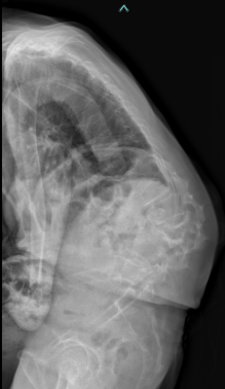

思春期特発性側弯症の全脊椎レントゲンで背骨が大きくSの字に曲がっています。最も曲がっている箇所は80°で、高度側弯に分類されます。後方からの脊柱側弯矯正術で真っ直ぐになっています。

また、側弯の患者さんは一般的にフラットバックと言って背骨の生理的後弯(背中の丸み)が失われています。この症例も胸椎後弯角は5°で典型的なフラットバックを呈しています(正常は20°~30°程度です)。この影響は頸椎の形態にも影響を及ぼし、この症例も頸椎が既に後弯(正常は前弯)しています。(黄色矢印)

ストレートネックという頸椎の前弯が消失して頸部の愁訴が出現する病態は広く知られていますが、更に変形が進行した頸椎と考えて下さい。

以前はこのフラットバック(生理的胸椎後弯の消失)を治すことは困難でしたが、当院では手術方法の様々な工夫により生理的胸椎後弯の復元を行っております。この症例は術後に胸椎後弯角が26°と改善しており、生理的な胸椎後弯が形成されています。さらに頸椎後弯にも良い影響を及ぼし、術後は頸椎前弯化が得られつつあるのが分かります。(黄色矢印)

他、側弯変形は必ず大なり小なりの回旋変形を伴います。脊柱の回旋変形は胸郭(肋骨)の回旋につながり、これにより側弯の患者さんは背中の片方が出っ張っています(多くは右)。リブハンプと言いますが、脊柱変形矯正によりこの回旋変形も改善します。この症例も術前に肋骨がかなり隆起していますが、術後にこの隆起がかなり減じているのが分かります。(赤矢印)